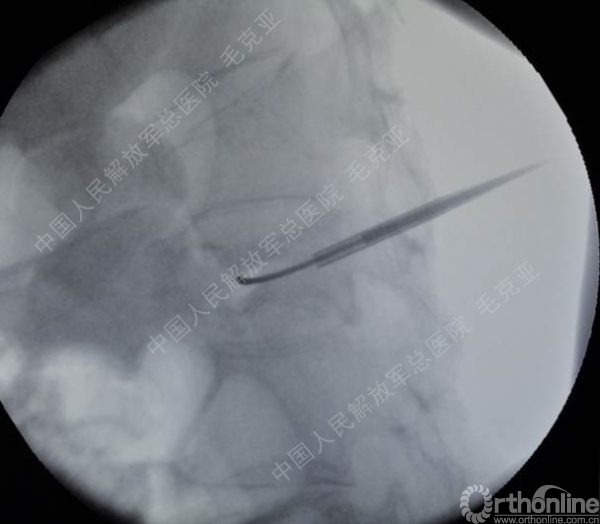

导语:随着社会老龄化的不断加速,骨质疏松性椎体压缩骨折作为一种普遍存在的老年骨科疾病已经成为现今骨科界的一个热点话题。传统的保守疗法治疗效果不佳,而现有的椎体增强技术又具有多种风险和缺陷。针对这种现状,中国人民解放军总医院毛克亚教授提供了一种新的解决方法。